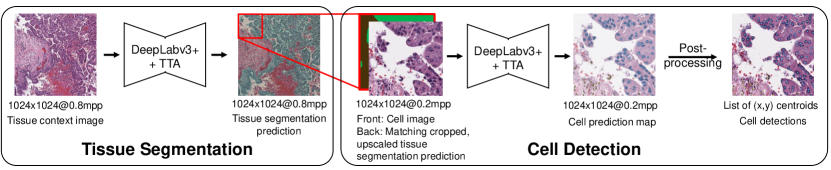

3.7 Combined Cell-Tissue Model

We combine the cell detection and tissue segmentation models, by providing and re-training the cell detection model with both the cell patch and the cropped and upsampled tissue segmentation prediction as input (Figure 4). The cell detection model ground truth configuration is chosen based on the best performance on the OCELOT validation set. Additionally, we evaluated the effect of geometrical TTA for more robust predictions, consisting of all 8 possible rotation and flip combinations. TTA was applied for both models.